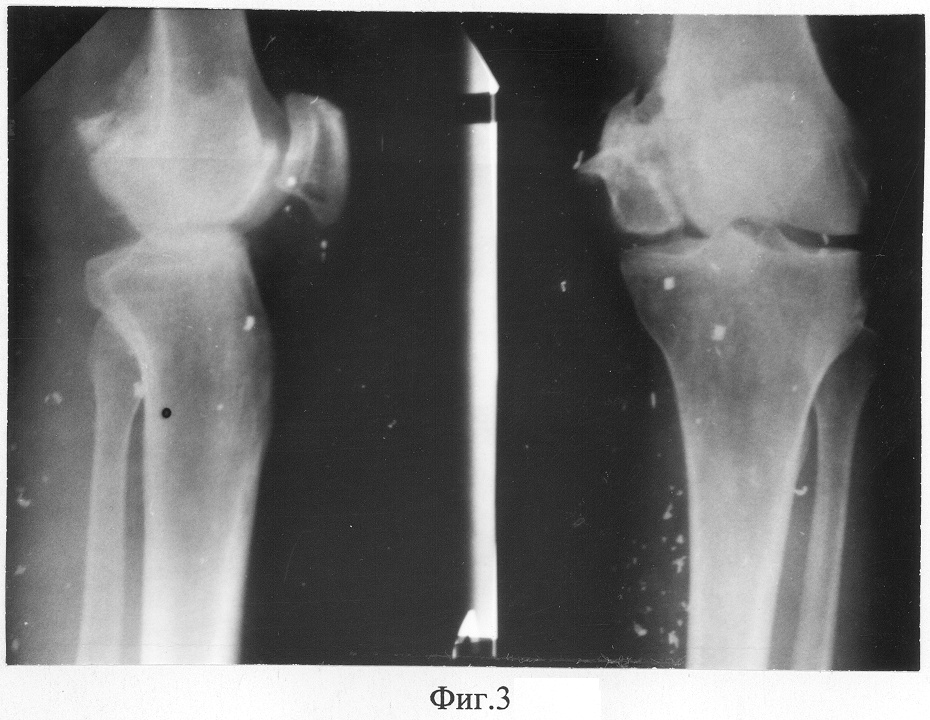

Фиг.3 – рентгенограммы коленного сустава пациента в прямой и боковой проекциях до лечения;

Жалобы: на боли в коленном суставе при ходьбе, хромоту, неустойчивость голени, ограничение объема движений в коленном суставе. При клиническом обследовании: варусное отклонение голени на 10° при нагрузке на ногу, сгибательно-разгибательная контрактура (65°-165°), болезненность при пальпации по внутренней поверхности коленного сустава. На рентгенограммах левого коленного сустава (Фиг.3): нарушение конфигурации суставных поверхностей левого коленного сустава вследствие неправильно сросшегося перелома внутреннего мыщелка левой бедренной кости, варусное отклонение голени 10° во фронтальной плоскости, явления гонартроза II ст. Суставная щель в медиальном отделе сужена, а в латеральном – расширена.